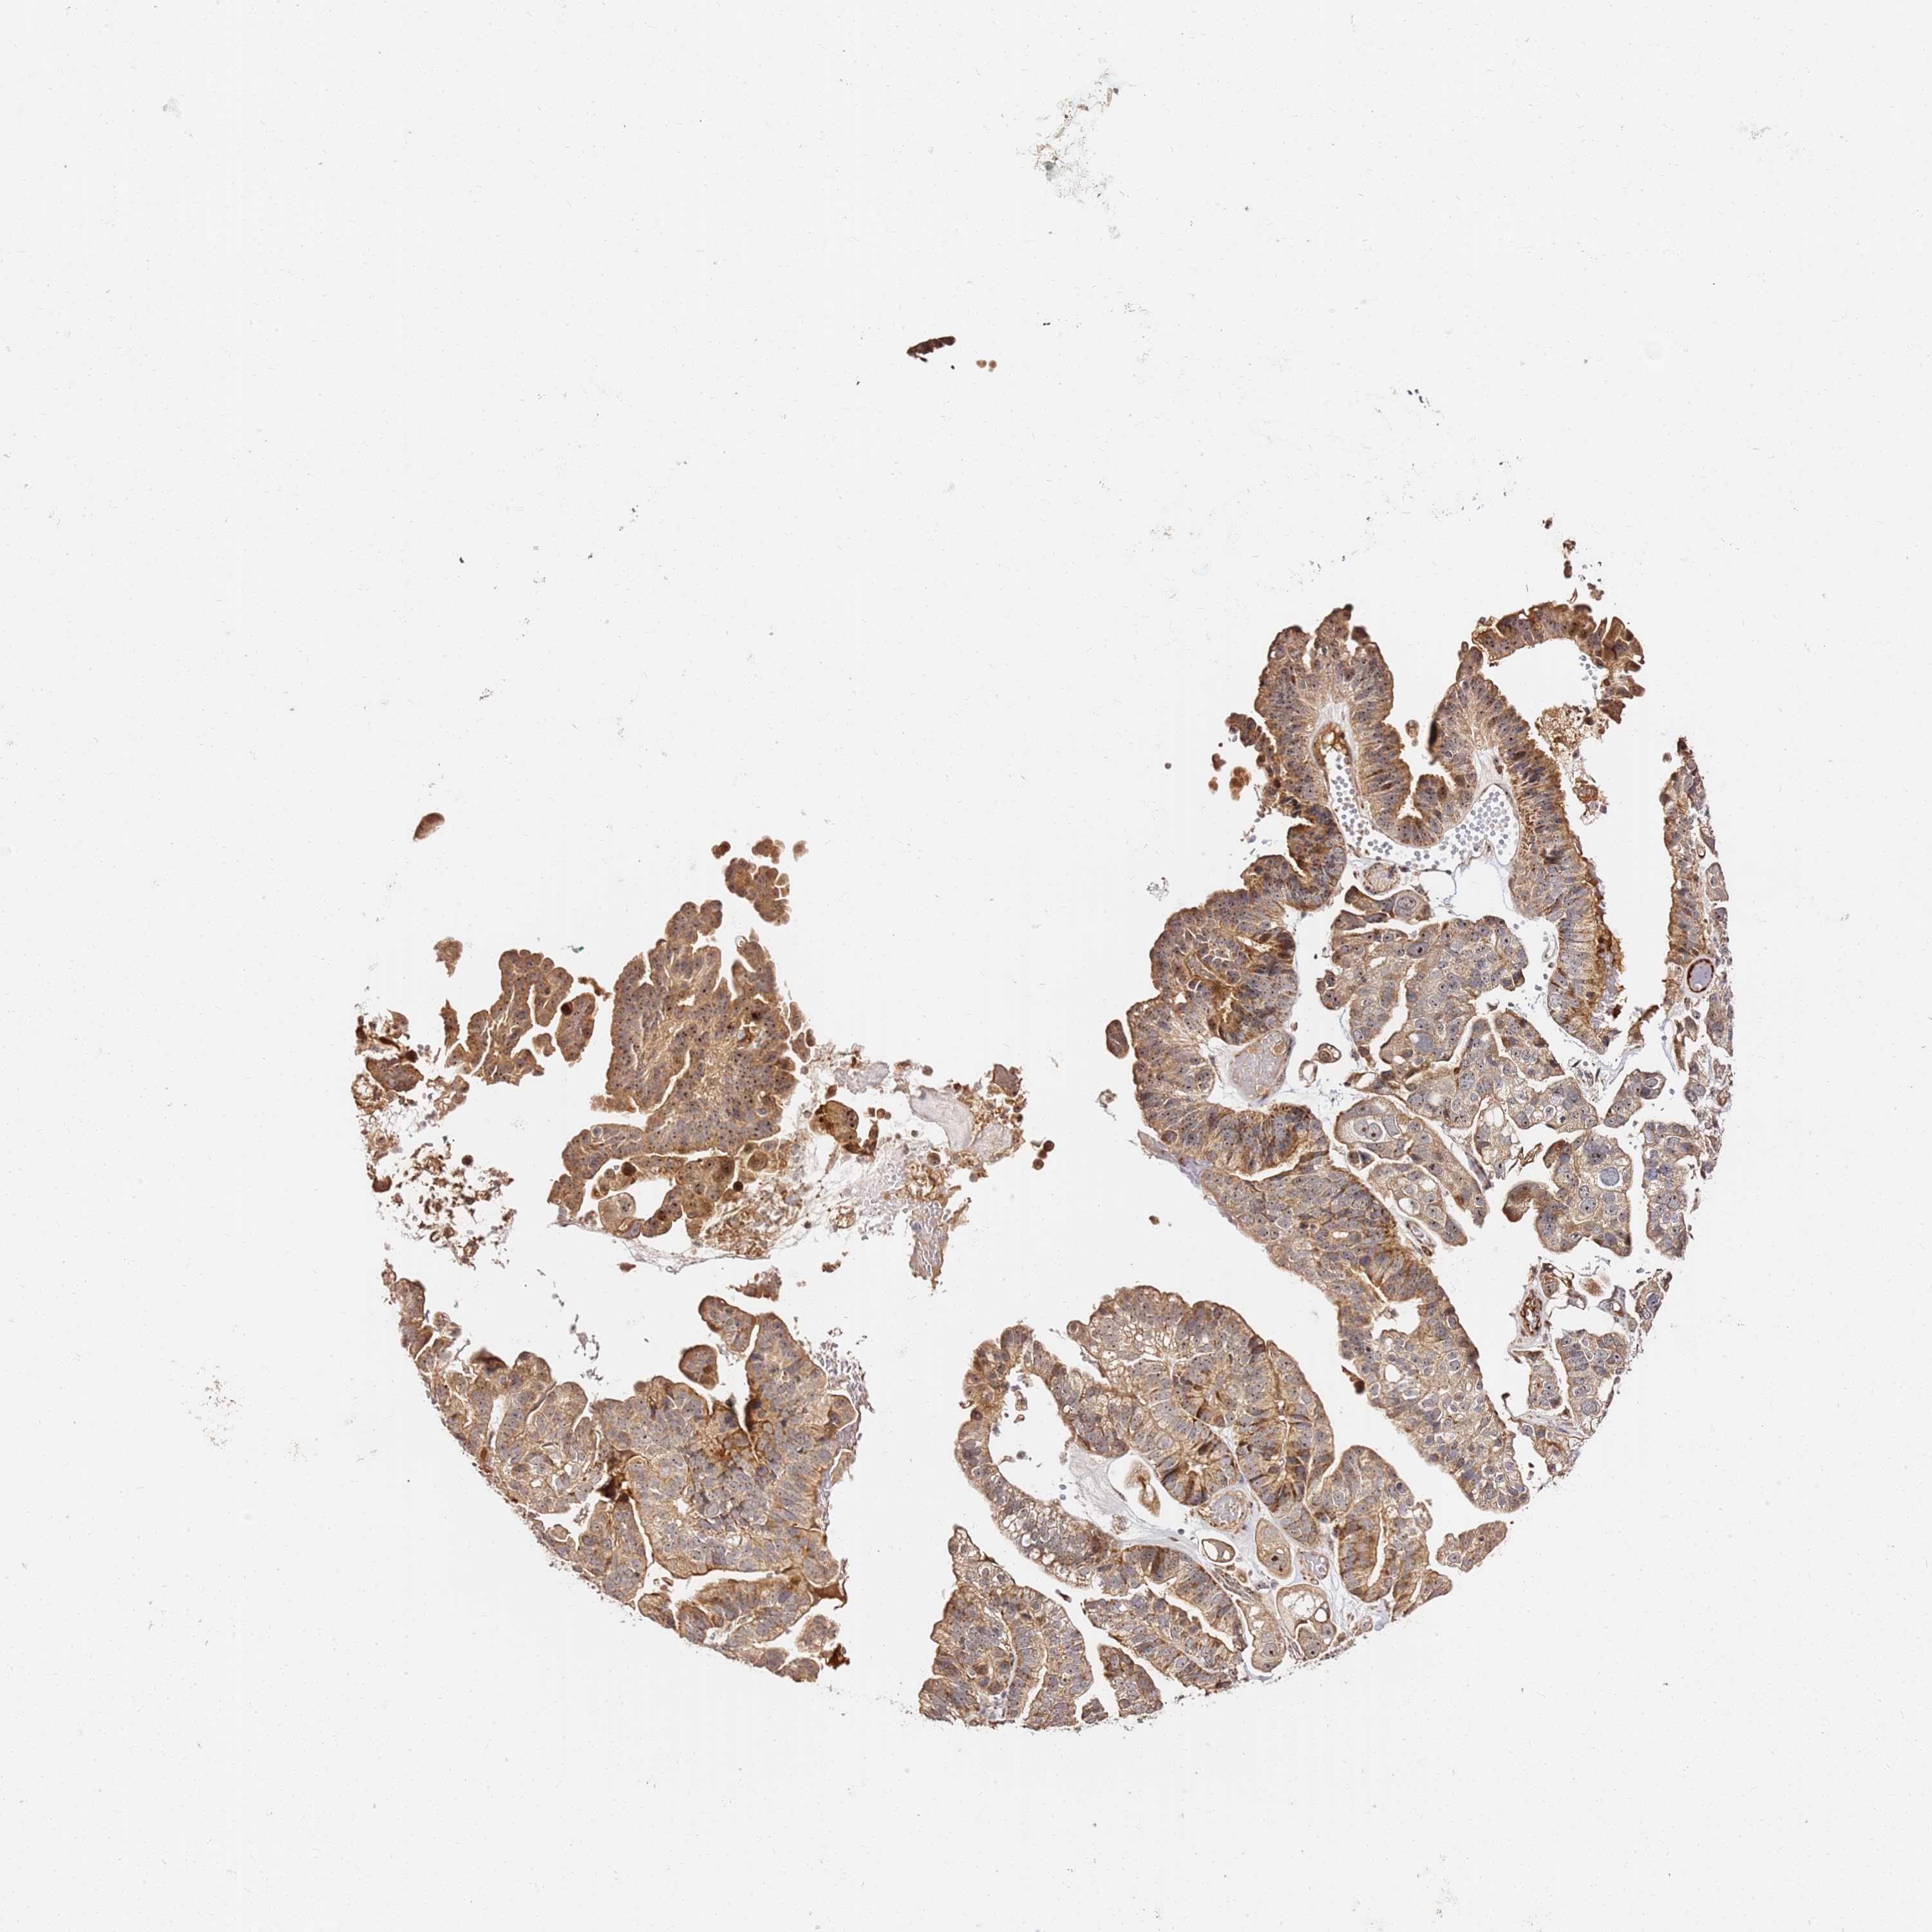

OVARIAN CANCER - Protein expressioni

A mouse-over function shows sample information and annotation data. Click on an image to view it in a full screen mode. Samples can be filtered based on level of antibody staining by selecting one or several of the following categories: high, medium, low and not detected. The assay and annotation is described here.

Note that samples used for immunohistochemistry by the Human Protein Atlas do not correspond to samples in the TCGA dataset.

Antibody stainingi

Antibody staining in the annotated cell types in the current human tissue is reported as not detected, low, medium, or high, based on conventional immunohistochemistry profiling in selected tissues. This score is based on the combination of the staining intensity and fraction of stained cells.

Each image is clickable and will lead to virtual microscopy that enables deeper exploration of all samples and also displays staining intensity scores, fraction scores and subcellular localization as well as patient and tissue information for each sample.

Antibody HPA046153

Staining

High

Medium

Low

Not detected

Intensity

Strong

Moderate

Weak

Negative

Quantity

>75%

75%-25%

<25%

None

Location

Nuclear

Cytoplasmic/membranous

Cytoplasmic/membranous,nuclear

Cystadenocarcinoma, serous, NOS

Carcinoma, endometroid

Cystadenocarcinoma, mucinous, NOS

Carcinoma, NOS